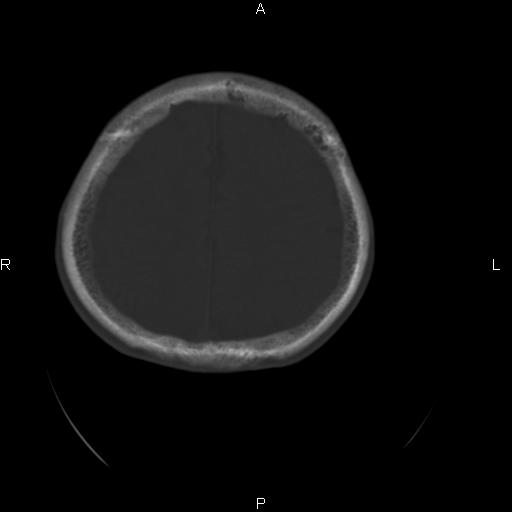

标题: CT27115:大家看一看,这孩子的颅骨表现? [打印本页]

标题: CT27115:大家看一看,这孩子的颅骨表现?

两名中学生打架,脑质内未见异常,未上传。

颅骨骨质未见异常。

颅骨未见骨折征象。

两例——颅骨结构正常,未见明显骨折征象。